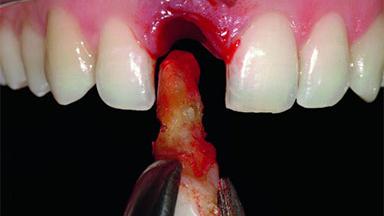

A 32-year-old female Caucasian patient with a compromised maxillary right central incisor was referred to us by a general dentist. Her chief complaints were discomfort and mobility of tooth 11 with unsatisfactory esthetics due to discoloration. The patient reported a previous trauma, some years earlier, as the origin of pathology on the afflicted tooth. Anamnesis was negative for any other dental or periodontal pathology in the remaining dentition. The patient did not take any medication and reported to be a light smoker (5–10 cigs/day). She had high esthetic expectations of her treatment. The extraoral examination revealed a high smile line with full exposure of her maxillary teeth and surrounding soft tissue in the area between the second premolars.

Bone Augmentation Horizontal|Simultaneous|Staged

Augmentation Materials Autogenous chips|Xenogenous|Membrane